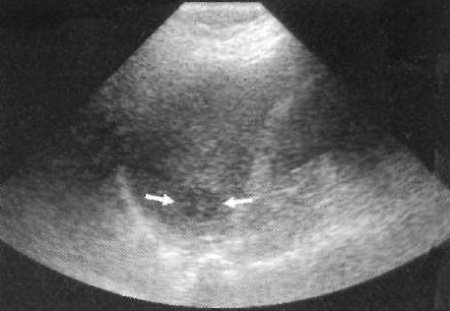

Ультразвуковая картина грибковых микроабсцессов характеризуется наличием образований, диаметром 5-10 мм (иногда до 2 см). Как правило наблюдается поражение печени и селезенки. На УЗИ их сложно обнаружить. Грибковые микроабсцессы могут визуализироваться как образования с центральным эхогенным узелком, окруженного гипоэхогенными кругами – картина «бычий глаз» (фото 3). Если в пределах центрального эхогенного узла возникает некроз, гипоэхогенный очаг может визуализироваться как «колесо в колесе».

Фото 3. Грибковый абсцесс селезенки по типу «бычий глаз». Стрелками обозначено образование с центральным эхогенным очагом, возникшее на фоне нейтропении с острой лимфоцитарной лейкемией. Аналогичное поражение у данного пациента выявлено и в печени

Методом выбора диагностики грибковых микроабсцессов селезенки является МРТ.